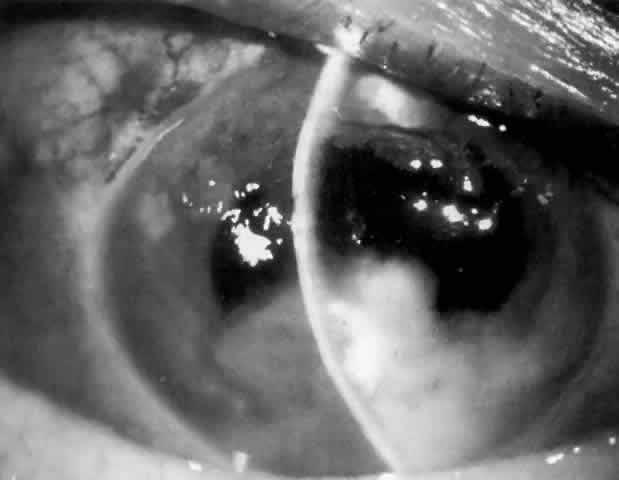

MANAGEMENT. The postoperative IOP elevation that occurs with the use of viscoelastic agents is exacerbated by cortical remnants and blood (Fig. 1). Careful cortical cleanup and aspiration of the viscoelastic agent may reduce the degree of IOP elevation. Prophylactic treatment of all patients (particularly those with preexistent glaucoma) with carbonic anhydrase inhibitors or beta-adrenergic blockers may decrease the incidence or severity of postoperative IOP elevation.35–38

Fig. 1. Hyphema and suspended blood in sodium hyaluronate (Healon) after extracapsular cataract extraction with posterior chamber lens implantation and trabeculectomy. Intraocular pressure is elevated, and there is microcystic corneal edema.